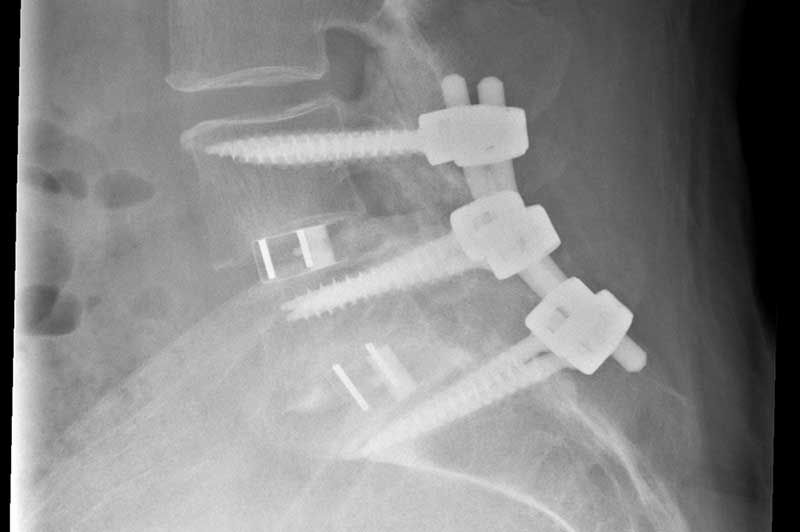

- Titanschrauben werden präzise in die Wirbelkörper eingebracht und mit Längsstangen verbunden

- Zur Versteifung wird Knochenmaterial auf den Querfortsätzen der Wirbelkörper und zwischen den Facettengelenken (Gelenke, die die Wirbelkörper verbinden) angelagert

Stabilisation der Wirbelsäule mit Titanschrauben und Knochenanlagerungen. Erweiterter Spinalkanal, um komprimierte Nerven freizulegen.

Zur zusätzlichen Stabilisation werden in vielen Fällen sogenannte Cages (Titankörbchen) mit Knochenmaterial in den Bandscheibenraum eingesetzt. Dieser Eingriff kann ebenfalls rückseitig oder über einen zusätzlichen seitlichen bzw. vorderen Zugang erfolgen.

Die eingesetzten Implantate stabilisieren die Wirbelsäule so lange, bis der angelagerte Knochen zu einer stabilen Versteifung führt. Eine spätere Entfernung der Titanmaterialien ist in der Regel nicht notwendig, da sie gut verträglich sind und nur selten Beschwerden verursachen.

Zusätzliche Stabilisation der Wirbelsäule durch Implantation von Cages zwischen den Wirbelkörpern